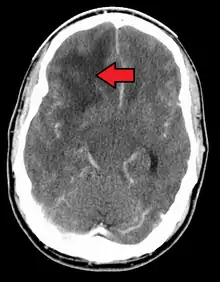

When viewed with MRI, glioblastomas often appear as ring-enhancing lesions. The appearance is not specific, however, as other lesions such as abscess, metastasis, tumefactive multiple sclerosis, and other entities may have a similar appearance.[58] Definitive diagnosis of a suspected GBM on CT or MRI requires a stereotactic biopsy or a craniotomy with tumor resection and pathologic confirmation. Because the tumor grade is based upon the most malignant portion of the tumor, biopsy or subtotal tumor resection can result in undergrading of the lesion. Imaging of tumor blood flow using perfusion MRI and measuring tumor metabolite concentration with MR spectroscopy may add diagnostic value to standard MRI in select cases by showing increased relative cerebral blood volume and increased choline peak, respectively, but pathology remains the gold standard for diagnosis and molecular characterization.